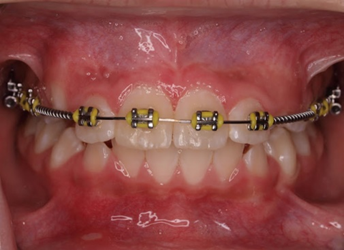

Răng thừa (a) làm R11 (b) bị kẹt không mọc ra được Tạo khoảng trước phẫu thuật

http://www.dentalnews.com/wp-content/uploads/2015/10/Maxillary-Central14.jpg =http://www.dentalnews.com/wp-content/uploads/2015/10/Maxillary-Central16.jpg =

Phẫu thuật lấy răng thừa sau 4 tháng tạo khoảng Chỉnh nha kéo R11 ngầm lên

Qúa trình chỉnh nha kéo răng cửa mọc ngầm hoàn tất

Hình 5: Minh họa phẫu thuật lấy răng thừa kết hợp với chỉnh nha ở một bé trai 9 tuổi